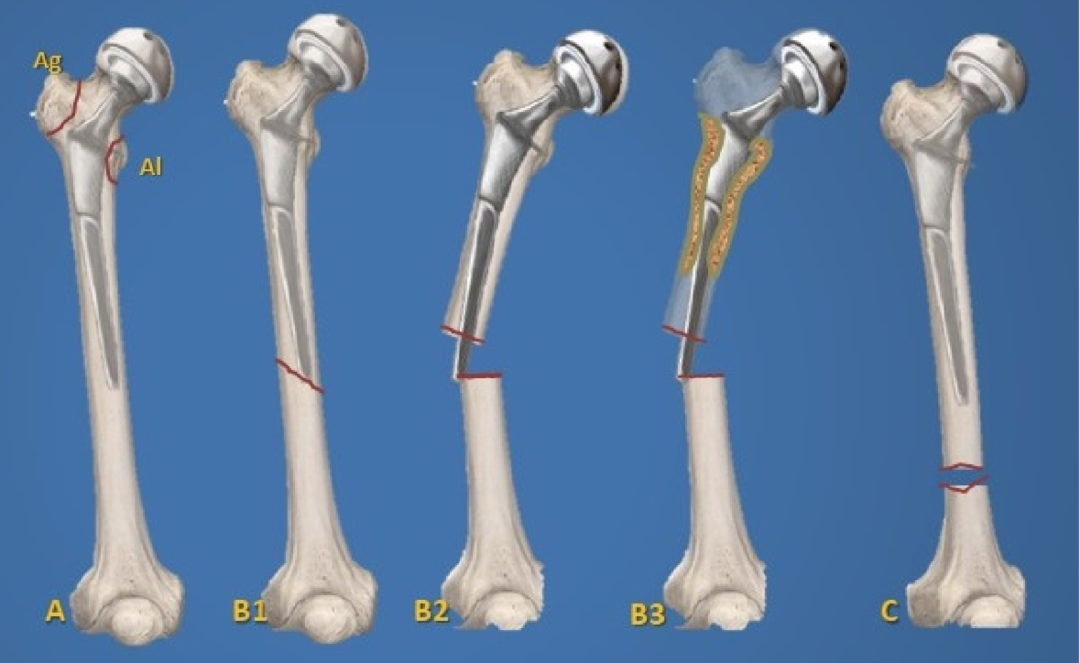

6. 假体周围骨折:

发病率 1%~2%。可发生在书中或术后。迟发性骨折多发生于股骨假体尖端。非骨水泥假体植入和翻修术更容易发生术中骨折。

Ag 型(累及大粗隆)

Al 型(累及小粗隆)

B1 型假体柄固定牢固

B3 型假体柄松动且伴骨质疏松

C 型骨折位于股骨假体尖端远处,假体稳定。